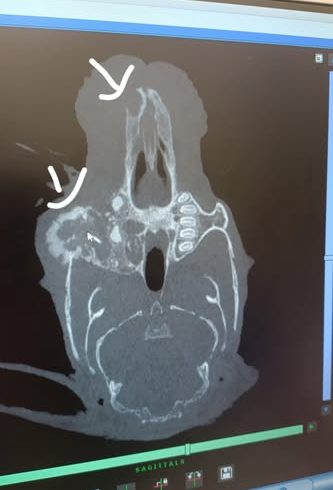

Vor einem Jahr kam sie zusammen mit ihrer Schwester zu uns. Ihre Schwester, die extrem klein war, ist bereits kurz darauf verstorben. Durch Inzucht hat auch Florea verschieden Baustellen. Sie ist kleinwüchsig, hat das Fell eines Babykaninchens und extreme Zahnfehlstellungen. Alle zwei Wochen mussten wir die Schneidezähne korrigieren, immer würde über einen OP zum Entfernen der Schneidezähne nachgedacht, aber sowohl wir als auch der Tierarzt hatten Bedenken wegen der Narkose. Vor 2 Monaten aber kamen wir um die OP nicht mehr herum und ihr wurden die oberen Schneidezähne sowie die oberen rechten Backenzähne entfernt. Sie hat die Narkose gut überstanden, hatte aber nach der Operation mit hartnäckigem Eiter zu kämpfen. Nach 4 Wochen war dann endlich alles gut verheilt. Nun kam vorletzte Woche der Eiter zurück und unser Tierarzt empfahl uns, ein Wach-CT machen zu lassen um zu sehen, was da los ist. Letzte Woche Montag war es dann soweit und die Ergebnisse sind niederschmetternd. Zwei ihrer oberen Backenzähne sind nachgewachsen, sie hat außerdem eine Verdichtung am rechten Jochbein, entweder durch eine starke Entzündung oder durch einen Tumor, dafür muss erst eine Probe entnommen werden. Auch die Nase ist auf Höhe des linken entfernten Schneidezahns verdichtet, auch hier muss nochmal aufgemacht werden. Die Ärztin ist in ihrer Prognose sehr vorsichtig und macht uns keine großen Hoffnungen. Auch unser Tierarzt sieht das so, er geht auch eher von einem Tumor aus, da sich Floreas Haut und Fell verändern. Nichtsdestotrotz wollen wir ihr eine Chance geben, der Termin für die zweite OP steht und danach wissen wir dann mehr. Sie wird nicht alt werden, aber ein bisschen Zeit hätte sie schon noch verdient!